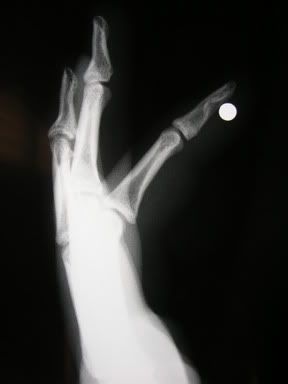

Not to sound like a worrywort, but just be careful out there. I had to pick this little nugget out of a guy who thought he blew his finger off until he realized how much pain he actually was in.